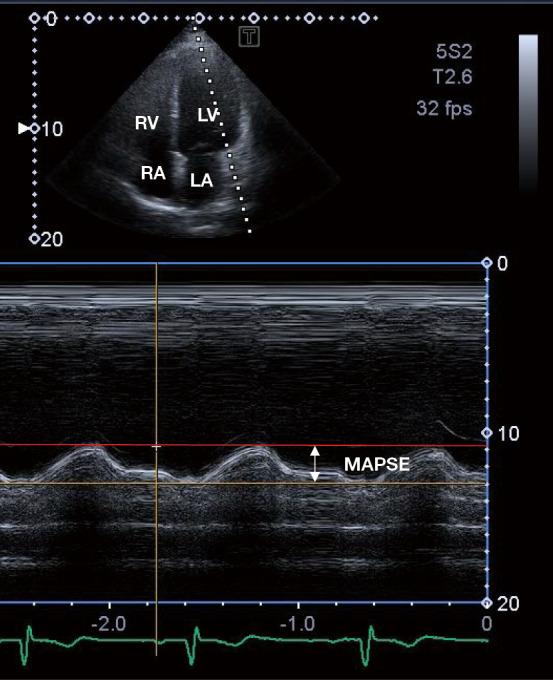

The mitral annulus (MA) is a fibrous ring with a three-dimensional (3D) movement during the cardiac cycle having an up-and-town longitudinal motion and a sphincter-like narrowing-dilating pattern respecting the cardiac cycle. In the clinical practice, the MA plane systolic excursion (MAPSE), a feature of MA longitudinal function, can be assessed by the simple and widely used M-mode echocardiography (MME), while changes of MA dimensions and derived functional properties can be accurately measured by 3D speckle-tracking echocardiography (3DSTE) at the same time. The aim of the present retrospective cohort study was to evaluate the associations between MME-derived MAPSE and 3DSTE-derived MA dimensions in healthy adults for better understanding their physiologic relationship.

二尖瓣环(MA)是一个纤维环,在心动周期中具有三维(3D)运动,呈现上下纵向运动以及类似括约肌的收缩-舒张模式,与心动周期相关。在临床实践中,二尖瓣环平面收缩期位移(MAPSE)作为二尖瓣环纵向功能的一个特征,可通过简单且广泛应用的M型超声心动图(MME)进行评估,而二尖瓣环尺寸的变化及其衍生的功能特性可同时通过三维斑点追踪超声心动图(3DSTE)进行精确测量。本回顾性队列研究的目的是评估健康成年人中MME得出的MAPSE与3DSTE得出的二尖瓣环尺寸之间的关联,以更好地理解它们的生理关系。